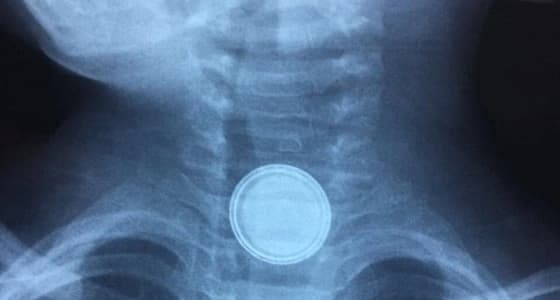

تمكن فريق طبي بمستشفى عرعر المركزي، من إنقاذ حياة طفل يبلغ من العمر سنتين، بعد ابتلاعه بطارية حديدية، علقت في بلعومه، بعد أن غفل عنه والديه.

جاء ذلك وفقًا لما أورده الحساب الرسمي للمديرية العامة للشؤون الصحية بمنطقة الحدود الشمالية، على " تويتر " ، حيث استطاع الأطباء إخراج البطارية من بلعوم الطفل في زمن قياسي، وذلك من خلال عملية ناجحة بواسطة المنظار.

وظهرت البطارية الحديدية التي ابتلعها الطفل بوضوح في إحدى الصور الشعاعية، فيما لفتت " الشؤون الصحية بالحدود الشمالية " ، إلى أن حالة الطفل باتت مستقرة.